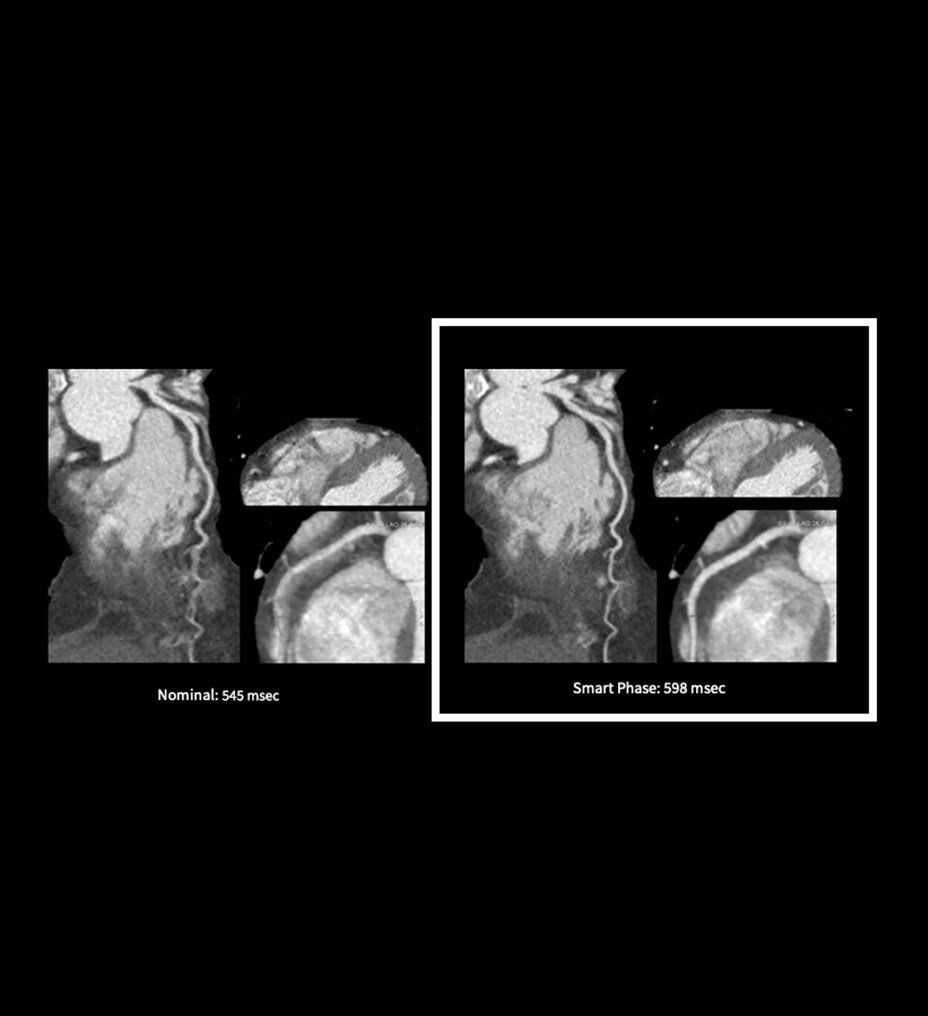

The ECG-less CT (a cardiac CT scan without an ECG trace) is an industry-first

Increases Cardiac CT access

Address cardiac exams where patient access and speed need to be prioritized

Simplified workflow

Useful in exams where excluding ECG traces would streamline patient preparation